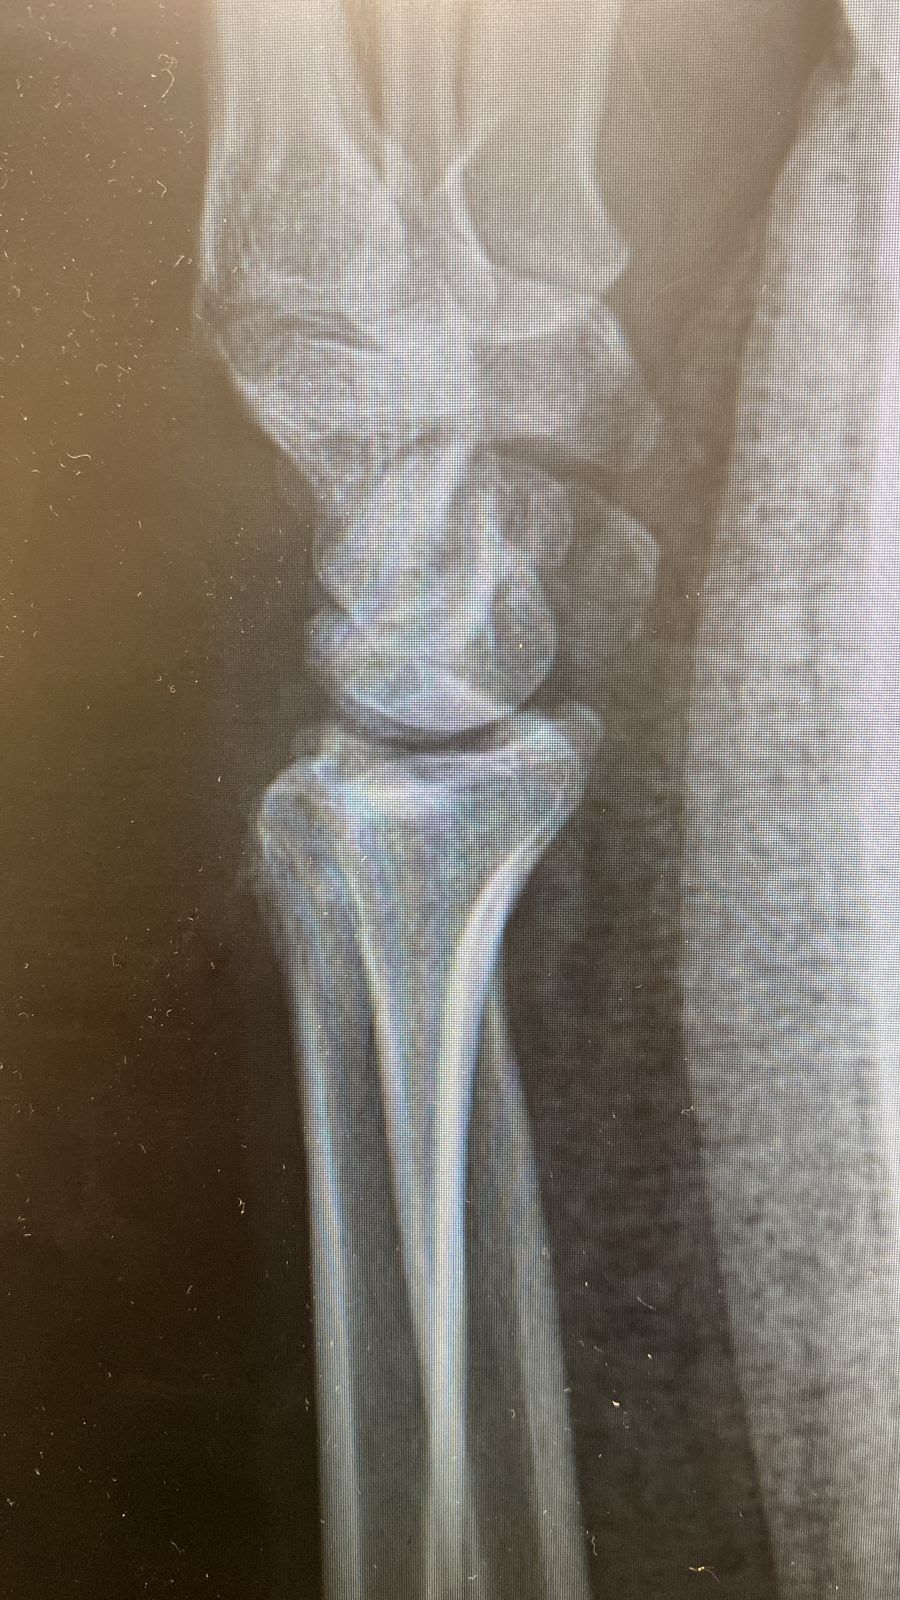

Um dos critérios radiográficos mais importantes a ser analisado consiste no

mal alinhamento carpal e análise do eixo axial. De acordo com diversos estudos publicados por McQueen et al. (1996), a falha na restauração do alinhamento carpal no plano sagital pode ser considerado o fator preditivo mais importante na deterioração funcional, tanto em questões funcionais quanto em termos de recuperação de força.

Mal alinhamento carpal existe quando o eixo longitudinal do capitato e do rádio realizam intersecção fora dos limites dos ossos do carpo.

Radiografia em perfil evidenciando (a) parâmetros utilizados para avaliar a presença de mal alinhamento radiocarpal e (b) fratura deslocada evidenciando mal alinhamento radiocarpal (Ng e McQueen, 2011).

Outra alternativa para analisar a presença do mal alinhamento carpal é o método da caixa radial ("Radial box"). O centro do capitato deve estar contido dentro de uma caixa definida pela cortical volar e dorsal do rádio, em uma incidência do tipo perfil verdadeiro do punho.